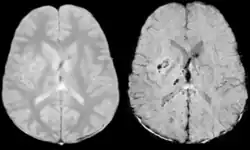

Comparison of diffuse axonal injury imaged with conventional GRE (left) and SWI (right) at 1.5 T

Comparison of hemorrhage imaged with conventional GRE (left) and SWI (right) at 1.5 T

The detection of micro-hemorrhages, shearing, and diffuse axonal injury (DAI) in trauma patients is often difficult as the injuries tend to be relatively small in size and can be easily missed by low resolution scans. SWI is usually run at relatively high resolution (1 mm3) and is extremely sensitive to bleeding in the gray matter/white matter boundaries making it is possible to see very small lesions increasing the ability to detect more subtle injuries.